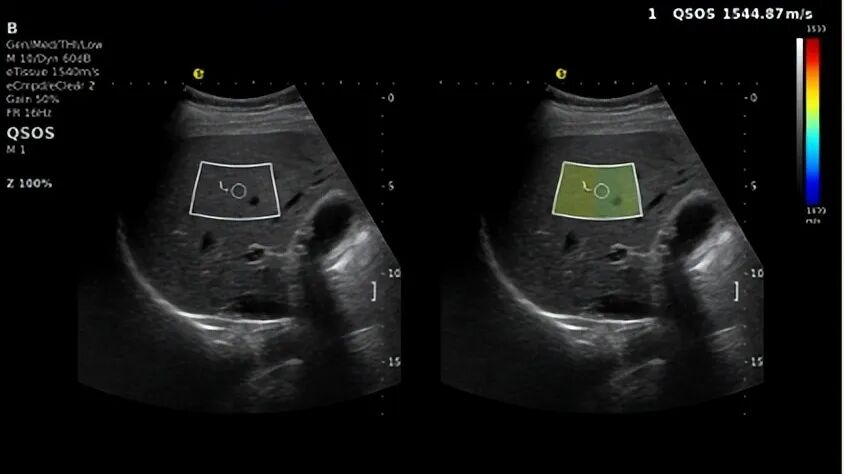

声速定量成像-QSOS®

作为早期损伤“探测器”的QSOS®声速定量技术,通过捕捉肝脏实质内声波传播速度的细微变化,能在纤维化萌芽阶段就发出预警,弥补了传统技术对早期肝损伤的漏判短板。